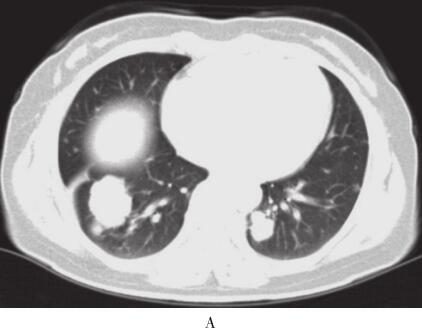

入院后体查未见阳性体征。辅助检查结果:血脂:甘油三酯为0.87mmol/L,总胆固醇为3.44mmol/L,高密度脂蛋自为0.85mmol/L,低密度脂蛋自为2.31mmol/L。ESR为29mm/ h。PPD试验及结核抗体阴性。血癌胚抗原(CEA)为0.6μg/ml。胸部增强CT示右下肺肿块约3.5cm×3.2cm,边缘呈分叶状,密度尚均匀,平扫CT值14HU,增强后30HU,双肺内还可见多个散在小结节影,左肺较大结节约1.5cm×2.0cm,边缘清晰,纵隔内未见肿大淋巴结(图1)。支气管镜检查示支气管炎症。痰及BALF未见异常细胞。入院后第1次CT引导下经皮右肺肿块穿刺活检病理示慢性炎症、纤维组织增生,可见胆固醇结晶沉积、富含脂质的巨噬细胞及较多空泡状细胞,上皮标记阴性,未见肿瘤细胞。全身PET/ CT显示右下肺前基底段团块状异常放射性浓聚影(3.2cm×4.2cm×3.5cm,最大SUV为6.4),双肺散在多个大小不等结节影,最大者位于左下肺后基底段,长径约2.2cm,最大SUV为3.8。第2次右下肺肿块穿刺活检,病理结果基本同前,病变符合外源性脂质性肺炎。

图1 2010年12月2日胸部增强CT

右肺肿块,双肺多发结节